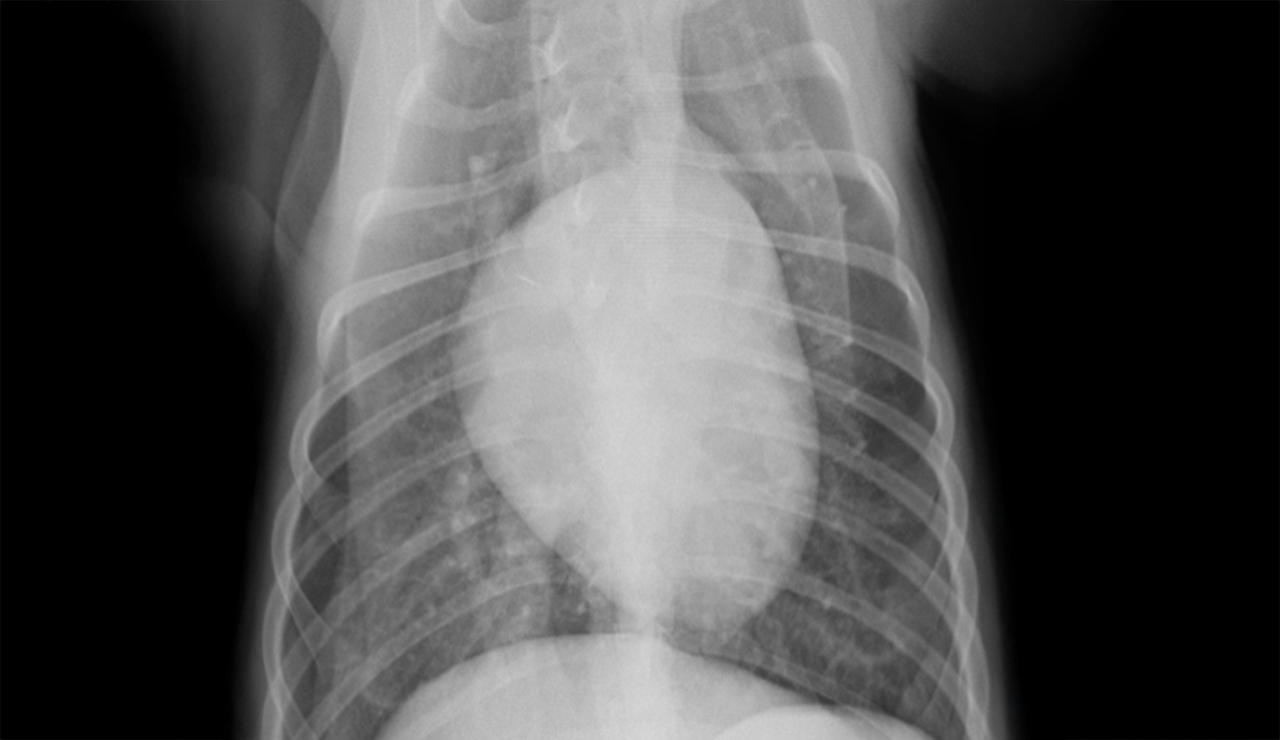

レントゲン検査装置 |

| X線の透過により、全身の骨、関節、肺、心臓、内臓の位置や形について異常を検出する装置。呼吸器疾患や整形疾患では特に重要な検査となります。 |